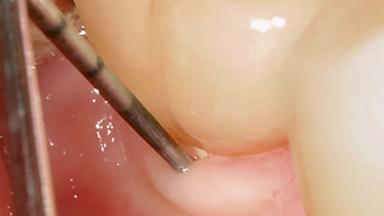

Treatment of Peri-Implantitis at a Zirconia Implant

Frank Schwarz, Ausra Ramanauskaite

Due to their promising clinical performance, zirconia implants have recently become popular alternatives to titanium implants, particularly for areas with high esthetic demands (Holländer and coworkers 2016; Roehling and coworkers 2016; Lorenz and coworkers 2019). However, regardless of the reported high survival and success rates, zirconia implants were affected by peri-implant diseases over the short observation period, suggesting the importance of treating peri-implant diseases at zirconia implants (Becker and coworkers 2017). In their case, Frank Schwarz and Ausra Ramanauskaite present 3-year results following mechanical debridement alongside Er:YAG laser monotherapy.